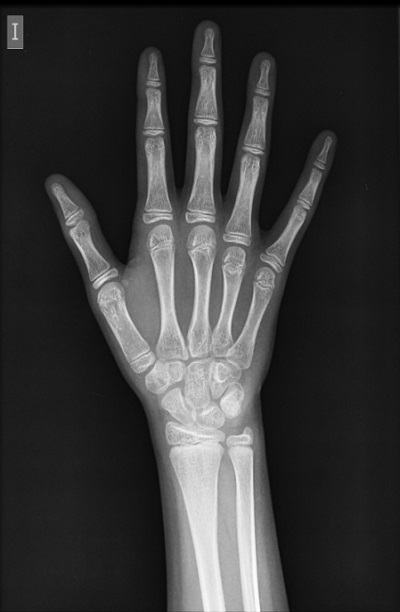

En la exploración presentaba acné inflamatorio comedoniano, mamas infantiles (estadio S1) y vello púbico escaso pigmentado (estadio S2), sin otros hallazgos. Se realiza una radiografía de mano y muñeca izquierdas (Fig. 1), que informa de una edad ósea correspondiente a diez años, hemograma, bioquímica y perfil tiroideo normales, valores de hormona luteinizante, hormona foliculoestimulante y estradiol prepúberes.

Figura 1. Radiografía de mano y muñeca izquierdas. Edad ósea de diez años (Atlas Greulich y Pyle)